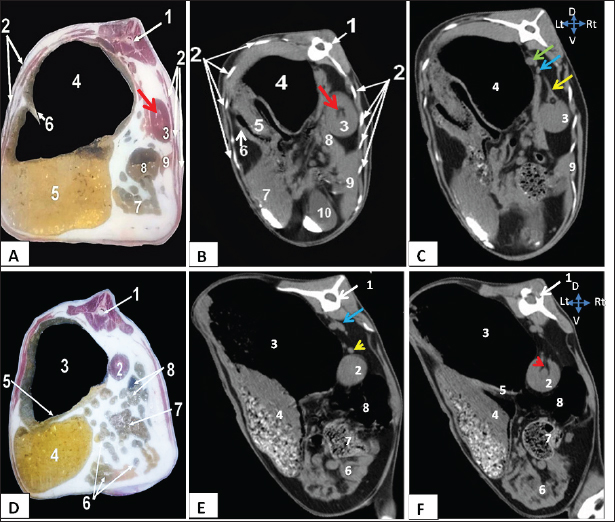

Both kidneys were readily distinguishable based on their morphology and associations in both anatomical and CT examinations (Figs. 2, 4). In both the transverse and dorsal planes of the CT scan, the objects exhibited a spherical to bean-shaped morphology.

On CT, both kidneys exhibited hypoechoic structures characterized by an anechoic hilus. A clear differentiation was observed between the cortex, medulla, and adjacent perirenal fat, particularly in the frozen sections.

On CT, both kidneys appeared ovoid and sharply demarcated with homogenous renal parenchyma. There was no sharp demarcation between the cortex and medulla, although the cortex was slightly denser than the medulla.

Figure 1 shows the visualization of the right kidney, located at the 12th thoracic vertebral level, specifically to the right of the median plane. The structure in question exhibited a dorsal relationship with the thoracic vertebrae, a lateral relationship with the ribs, a medical association with the dorsal ruminal sac, and an embedded location inside the renal impression of the caudate lobe of the liver.

The left solitary kidney was observed at the second lumbar vertebral level, positioned to the right of the median plane (Fig. 2). The dorsal ruminal sac, as observed in the dorsal-plane CT scan (Fig. 4), resulted in the displacement of the left kidney toward the right side of the abdomen and the caudal migration toward the right kidney. The left kidney exhibited a dorsal relationship with the lumbar spine, a medial relationship with the dorsal ruminal sac, and a ventrolateral relationship with the intervening intestine.

A dorsal-plane CT scan revealed the presence of the right renal vein, which extended from the right kidney toward the caudal vena cava (Fig. 4). Both transverse and dorsal plane CT scans revealed the presence of the right renal artery, which originates from the aorta and extends toward the right kidney (Figs. 2, 4). Following its entry into the renal hilus (Fig. 2), the structure underwent bifurcation into its dorsal and ventral branches. In the dorsal-plane CT scan, the right ureter was positioned dorsally adjacent to the caudal vena cava, extending toward the urinary bladder. The lumen was smaller in size compared with the renal vein (Fig. 4).

The egress of the left ureter from the left renal hilus was observed in the transverse CT image (Fig. 2). On transverse- and dorsal-plane CT scans (Figs. 3, 4), the urinary bladder may be identified at the sacrum level on the pelvic floor, located beneath the uterus and rectum. A dorsal-plane CT scan revealed the presence of the urethra exiting the urine bladder in a caudal direction (Fig. 4).

Fig. 2. Representative macrographic images of cross-sectional anatomy (Panel A-C) and CT image (5-mm thickness) (Panel B-D) of the goat abdomen. Panel A: 1- Twelfth thoracic vertebra; 2- Costal bony segments; 3- Right kidney; 4- Dorsal ruminal sac; 5- Ventral ruminal sac; 6- Right longitudinal ruminal pillar; 7- Jejunum; 8- Cecum; 9- Right lobe of liver; Red arrow: Renal hilus. Panel (B-C): 1- Twelfth thoracic vertebra; 2- Costal bony segments; 3- Right kidney; 4- Dorsal ruminal sac; 5- Ventral ruminal sac; 6- Greater omentum; 7- Abomasum; 8- Caudate lobe of liver; 9- Right lobe of liver; 10- Gall bladder; Red arrow: Renal hilus; yellow arrow: Right renal artery; Green arrow: Caudal vena cava; Blue arrow: Aorta. Panels (D-F): 1- Second lumbar vertebra; 2- Left kidney; 3- Dorsal ruminal sac; 4- Ventral ruminal sac; 5- Left longitudinal ruminal pillar; 6- Jejunum; 7- Cecum; 8- Colon; Blue arrow: Aorta; Yellow arrowhead: left renal artery; Red arrowhead: Left ureter.